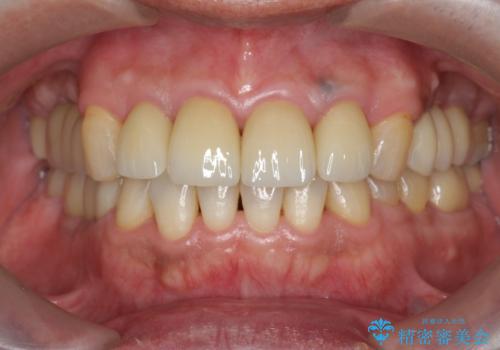

- 61.6万円(仮歯・ジルコニアクラウン×4・ファイバーコア ・エクストリュージョン)費用は治療当時の料金となります

虫歯の放置により、根管治療や深い虫歯に対する処置が必要になりましたが丁寧に一つづつ処置を行ったことで抜歯をすることなく歯を残すことができました。

セラミッククラウンの製作をする前に、歯内・歯周環境の整備は非常に大切です。